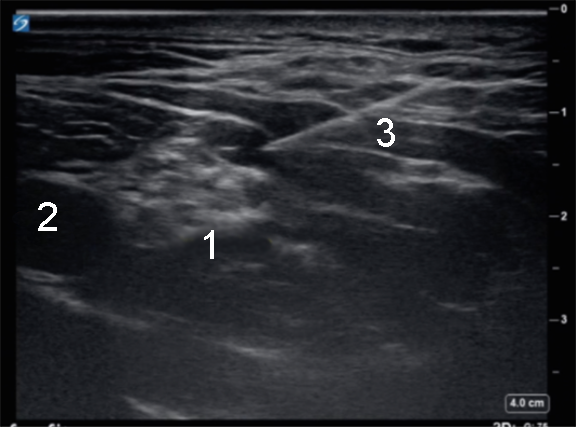

Supraclavicular Injection 2 Image

Brachial Plexus

Subclavian Artery

Needle